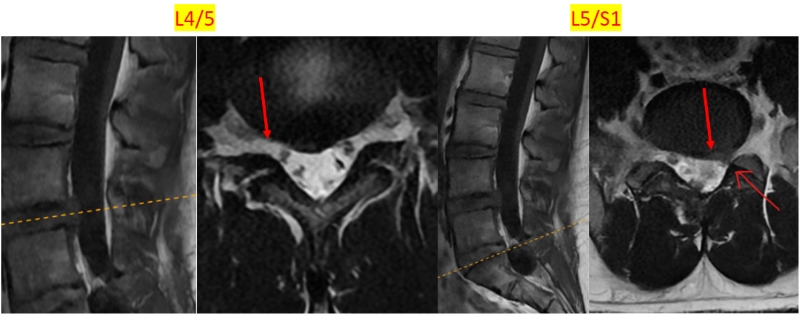

Qua thăm khám phát hiện ấn điểm gai sau, cạnh sống trái ngang mức L4/5 đau tăng rõ kèm tình trạng hạn chế gấp duỗi, nghiêng xoay cột sống thắt lưng nhẹ do đau. Đặc biệt, trên hình ảnh chụp MRI cột sống thắt lưng cho thấy đĩa đệm L5/S1 có tình trạng phồng, chèn ép rễ thần kinh bên trái. Chẩn đoán xác định, tình trạng của bệnh nhân bao gồm viêm dây chằng liên mỏm gai, phồng đĩa đệm L4/5, L5/S1 có chèn ép rễ, nang Tarlov cột sống thắt lưng.

Hình ảnh chụp MRI cột sống thắt lưng cho thấy tình trạng bất thường vùng đĩa đệm